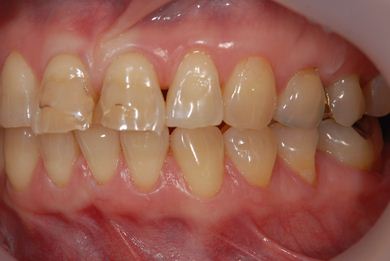

治療後

• 治療後